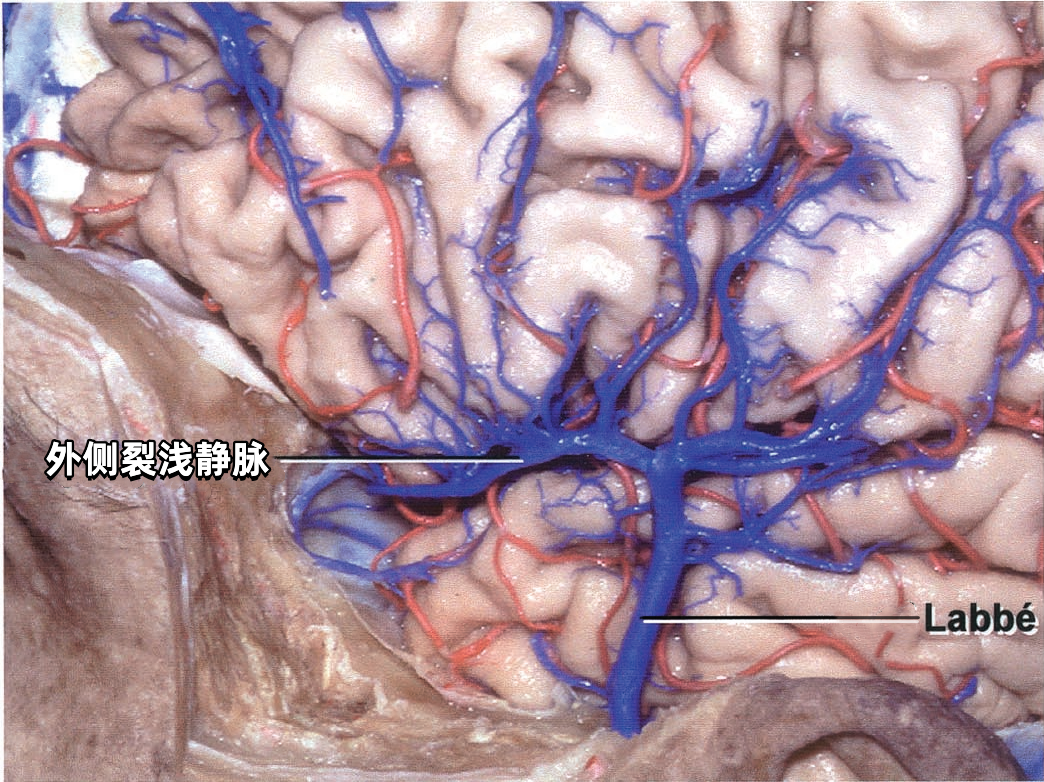

3. 提高手术安全性:尤其关键静脉(如Labbe静脉、中央沟静脉、深部静脉系统)的保护直接影响预后。

癫痫(Labbe静脉损伤后颞叶水肿)。

学习RHOTON解剖,对脑静脉系统的深入理解,有助于手术的安全操作。